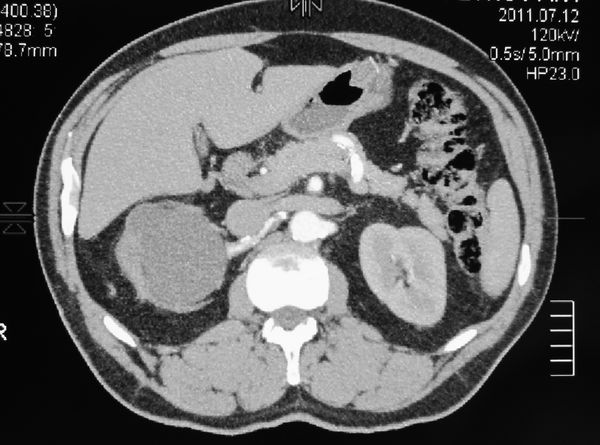

Гидронефротическая трансформация правой почки. Паренхима источнена. ее практически нет.